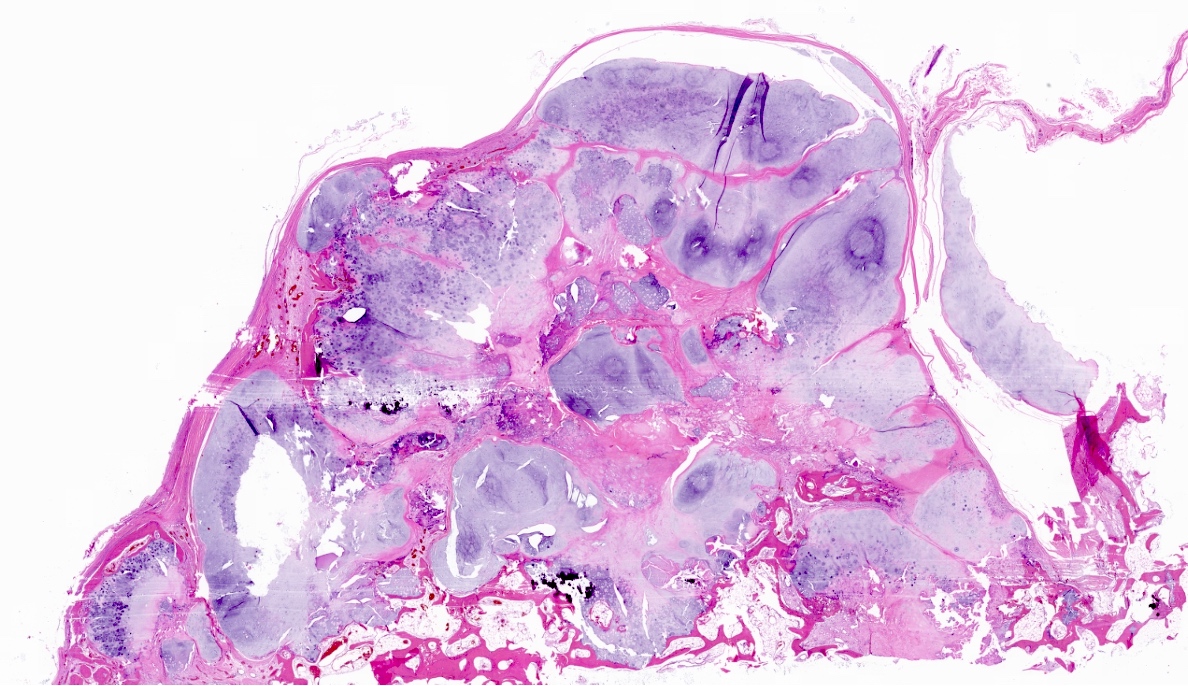

Microscopic (histologic) description

- Lobulated growth pattern (J Dent Res Dent Clin Dent Prospects 2011;5:98)

- Lobules have irregular shapes and sizes and may be separated by fibrous bands containing small vessels (Virchows Arch 2012;460:95)

- Lobules are composed of abundant hyaline cartilage matrix (sometimes with mucoid / myxoid changes) and permeate and entrap lamellar bone trabeculae

- Cellularity is slightly higher than in enchondroma

- Cells show moderate eosinophilic to vacuolated cytoplasm

- Nuclei are small and uniform with condensed chromatin (lymphocyte-like); sometimes they show open chromatin with visible nucleoli (Am J Surg Pathol 2009;33:50)

- Mitoses and significant nuclear pleomorphism are absent

- Binucleation can be observed

- Necrosis can be seen

- In cases arising from pre-existing enchondromas, areas of enchondroma with calcifications can be present

- In cases arising from pre-existing osteochondroma, evidence of this tumor can be seen (Mod Pathol 2012;25:1275)

Microscopic (histologic) images

- Bone, left 5th and 4th metatarsals, excision:

- Atypical cartilaginous tumor (see microscopic description)

- Microscopic description: Examination of the histopathologic sections reveals mature trabecular bone with juxtaposed cartilaginous proliferation, characterized by low to moderate cellularity, chondrocytes with occasional binucleated cells and mild atypia in a hyaline cartilage matrix. Foci of necrosis, nonischemic type are seen. Given the presence of nonischemic type necrosis, the large size of the tumor and the cellular atypia, the tumor is most consistent with atypical cartilaginous tumor that may have arisen from an osteochondroma.

Practice question #1

A 41 year old woman complained of an enlarging mass at her left proximal humerus. Xrays showed a lucent lesion with indistinct borders and endosteal scalloping. MRI showed an irregular, expansile, avidly enhancing mass. A biopsy of the lesion was performed and is shown above. What is the diagnosis?